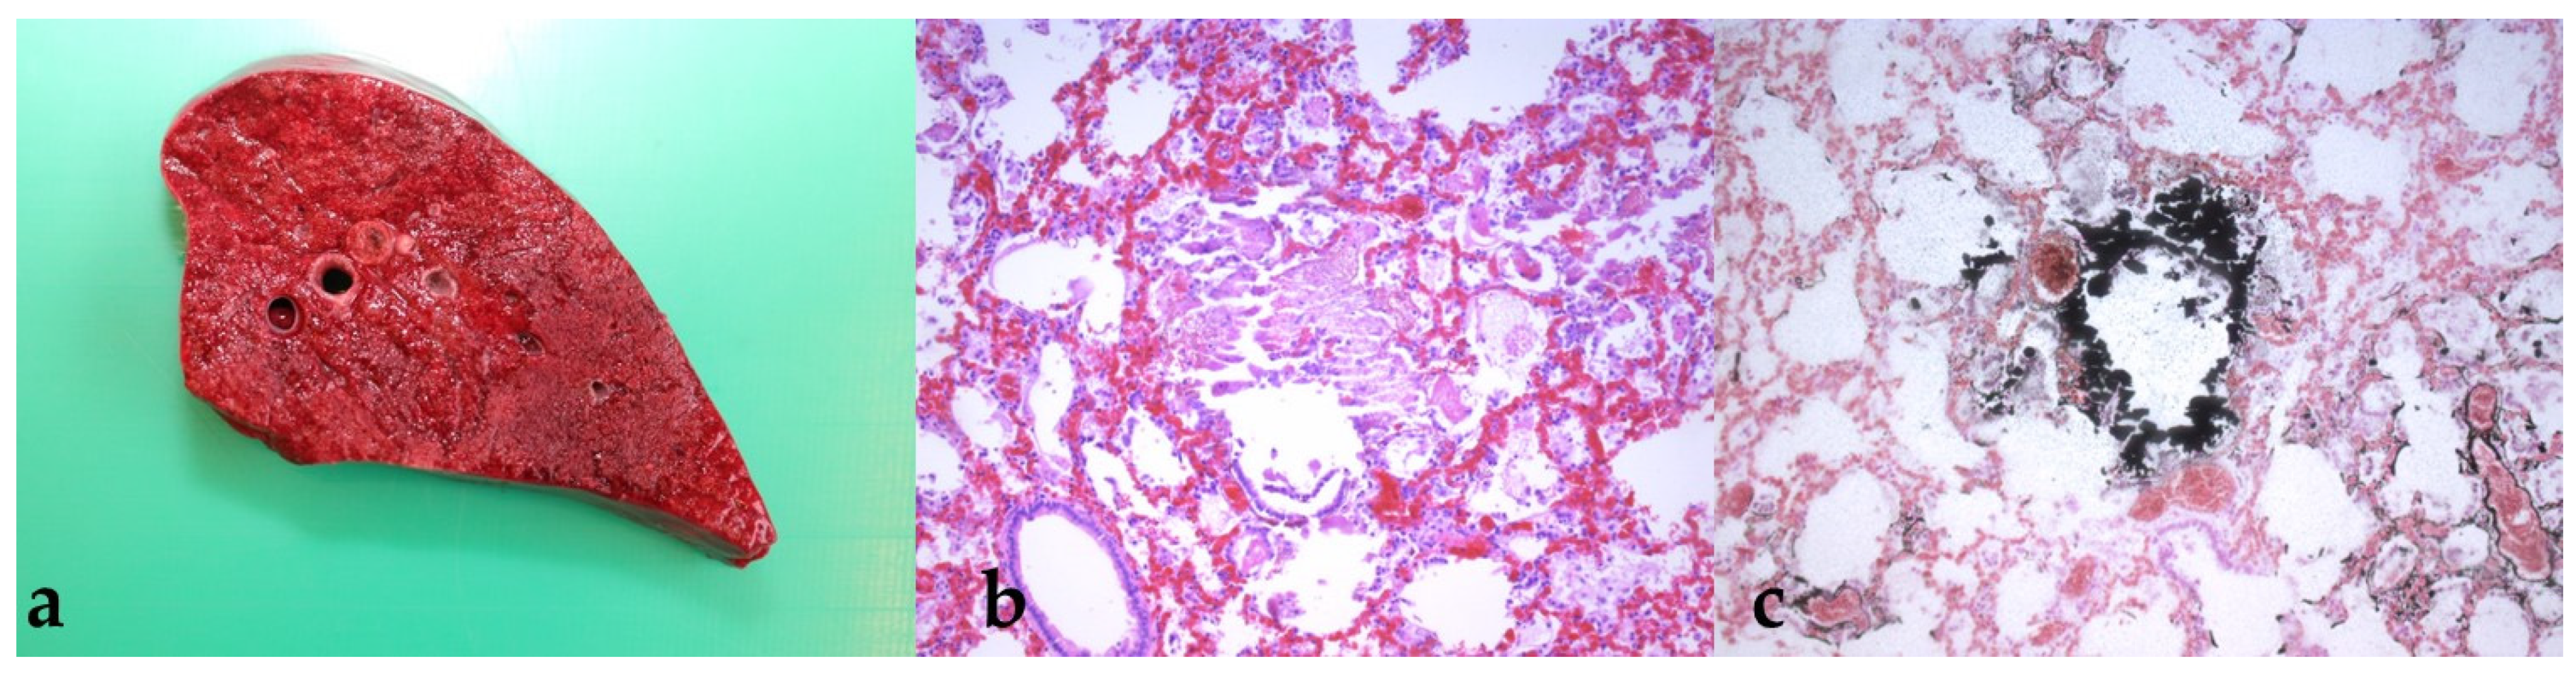

3.4. Findings from the Pathological Examination